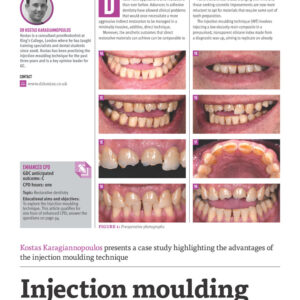

The injection moulding technique aims at replicating a pre-approved shape when restoring teeth in resin composite. It is a systematic approach designed to put the clinician in total control of their outcomes. The course has been designed and updated with the dentist in mind after feedback from hundreds of previous delegates. The key words that describe injection moulding are predictability, consistency and simplicity.

Explain and demonstrate the Injection Moulding technique for composite resin

Discuss step by step technical and clinical processes

Discuss materials available, alternative techniques and evidence about injectable resin composites